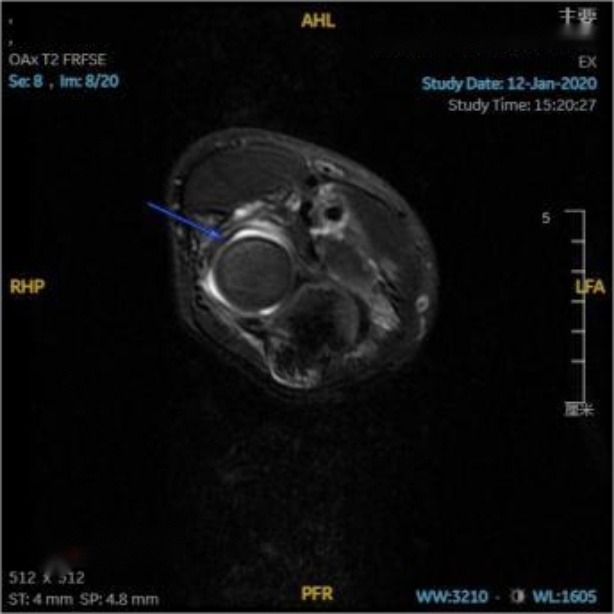

在对照MRI影像横断位,可见环绕桡骨头的环状韧带连续性完整,与桡骨头间充满高信号韧带下积液(见图3(a)图3(b)蓝箭头);在对照MRI影像冠状位(见图3(c)蓝箭头),可见关节腔内充满高信号的关节积液,积液内可见一明显低信号带状影,未见低信号影嵌入关节内,提示环状韧带连续性良好未嵌入肱桡关节内;在对照MRI影像矢状位(见图3(d)图3(e)蓝箭头),可见肘关节内有高信号的关节积液,关节间隙旁可见一低信号带状影,形状完整,连续性良好,并未嵌入关节间隙内。

放射学复位后,即复位后X片提示桡骨干轴线无明显偏离肱骨小头骨化中心,但患儿仍存在肘关节活动受限,此种情况即视为解剖学复位失败,其MRI影像表现为:横断位可见环状韧带局部变薄,与桡骨头之间可见高信号积液,韧带局部不再环绕桡骨头,与桡骨头交界处模糊(见图4(a)红箭头);冠状位可见环状韧带局部变薄,疑似连续性中断,脱套的环状韧带呈低信号,其上半部分卡压于肱桡关节间隙中,关节间隙内见带状液性高信号,关节周围可见软组织肿胀(见图4(b)红箭头);矢状位可更直观清晰的看到在关节间隙中的高信号关节积液衬托下,嵌入肱桡关节内的低信号环状韧带;除此之外也可见尺骨鹰嘴近端骨皮质信号不连续,断端间对位对线良好,整个左肘部周围肌肉均有广泛肿胀(见图4(c)红箭头)。